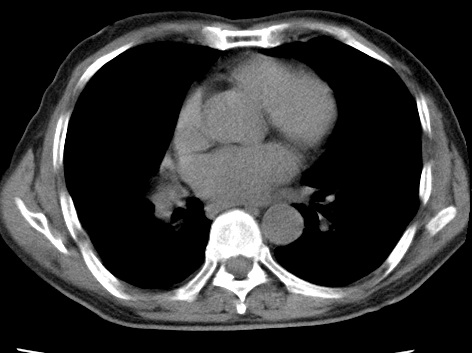

考虑右肺中叶不张,请大家发表意见

右肺中叶不张、肺门轮廓增大,占位不除外;建议增强,必要时支气管镜详查。

右肺中叶支气管闭塞,中叶肺不张,右侧肺门见肿块影。中心型肺癌的可能大。建议支气管镜检查。

右中叶体积明显缩小,且其支气管未显示,先考虑:中心型肺癌班右中叶肺不张。

建议:支气管镜检查。

考虑右肺中叶中央型肺癌并右肺中叶肺不张;建议:行纤支镜检查。

右肺门旁类圆形肿块影,右肺中叶不张,建议纤支镜检查。

1右肺门旁类圆形肿块影,右肺中叶不张,建议纤支镜检查

2右侧胸膜增厚,右侧叶间胸膜区钙化

3右肺下叶小囊状透亮影考虑肺气肿